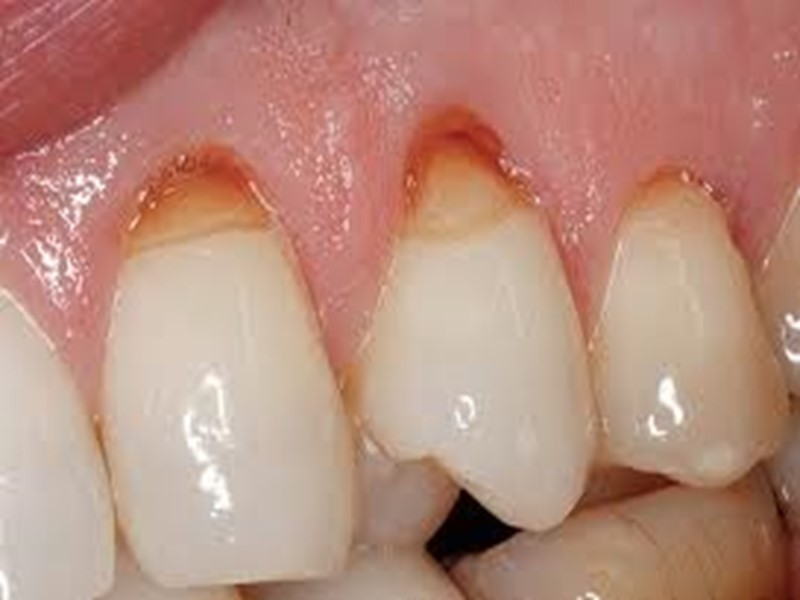

Классификация по локализации: Фиссурный кариес. Контактный (апроксимальный) кариес. Пришеечный (цервикальный) кариес. Циркулярный (кольцевой) кариес.

Поверхностный кариес дифференцируют с: Системной гипоплазией (бороздчатая форма) Флюорозом (эрозивная форма) Эрозией эмали Клиновидным дефектом Кислотным некрозом

Дифференциальная диагностика поверхностного кариеса с эрозией эмали и клиновидным дефектом Общее: - жалобы на эстетический дефект; - кратковременные боли от химических, термических раздражителей; - возникновение после прорезывания зуба; - прогрессирующее течение; - наличие дефекта твердых тканей зуба в пределах эмали; - болезненное зондирование.